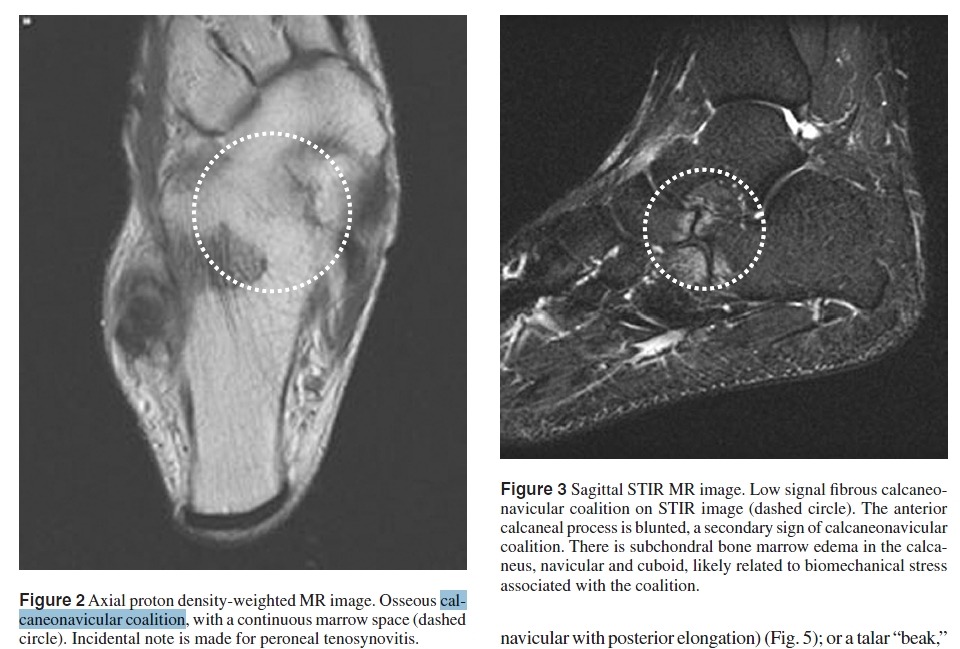

Calcaneonavicular Coalition

Figure 19 Coalition.

(A) Calcaneonavicular coalition. Lateral view of the ankle shows a talar beak (arrow), which is often

associated with coalition. Note the “anteater sign,” in which the anterior calcaneal process (arrowheads) continues into

the navicular bone, caused by a coalition.

(B) Calcaneonavicular coalition. Lateral oblique view of the foot of the same patient as (A) optimally depicts the site of calcaneonavicular coalition (arrows).

(C) Subtalar coalition. Lateral view of the ankle shows a talar beak (arrow) and a “C sign” (arrowheads) caused by a prominent sustentaculum tali seen in the setting of subtalar coalition

(D) Subtalar coalition. Harris–Beath view of the same patient as (C) shows bone prominence at the sustentaculum tali (arrow) and lack of visualization of the middle facet compared with the posterior facet (arrowhead), which should be in the same plane.

tasal coalition에 대한 mri자료

첨부파일 MRI of Tarsal Coalition.pdf